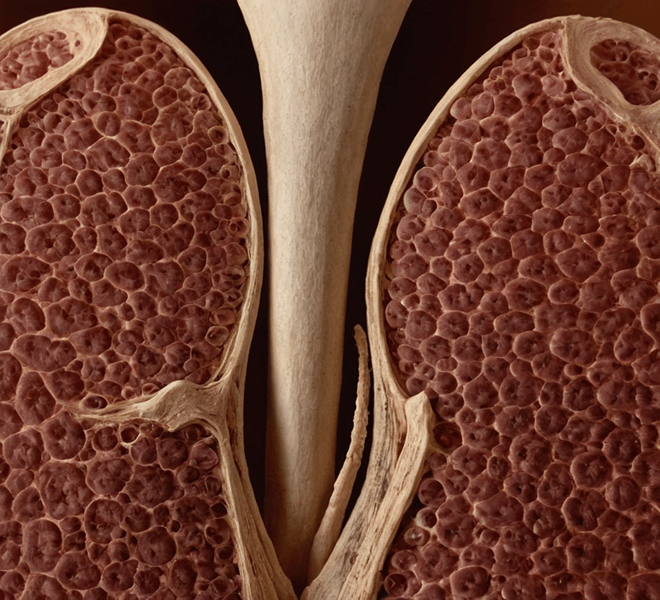

Coxofemoral luxation, or hip dislocation, occurs when the femoral head displaces from the acetabular socket in the hip joint. Both hips can be affected, leading to bilateral luxations. Major stabilizers of the hip joint include the joint capsule, ligament of the head of the femur, and the dorsal acetabular rim, while minor stabilizers include the ventral acetabular ligament, gluteal muscles, hip adductors, and hip abductors. At least two major stabilizers must be disrupted for luxation to occur.